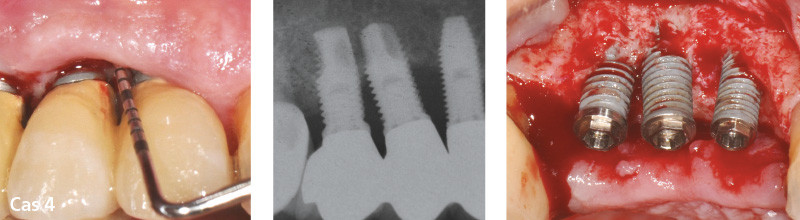

Les péri-implantites avancées : traiter ou déposer ?

Les péri-implantites sont pour la plupart asymptomatiques et le diagnostic est souvent tardif. Le praticien est donc confronté à des pertes osseuses péri-implantaires souvent sévères pouvant représenter plus de la moitié de la hauteur de l’implant. De plus, la morphologie des lésions osseuses associées peut être plus ou moins complexe.

– de proposer différentes techniques de traitement, de dépose et de réaménagement des défauts osseux associés.

Il est donc logique de se poser la question, face à une péri-implantite sévère, de la conservation ou de la dépose de l’implant atteint. Il n’existe aujourd’hui dans la littérature aucun arbre décisionnel concret pour cette prise de décision : traiter ou déposer ?